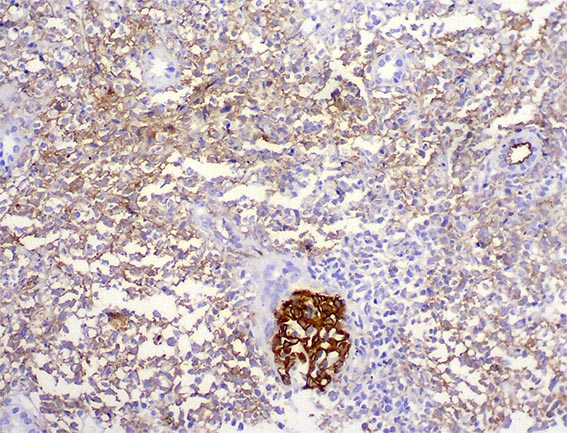

La inmunohistoquímica demostró positividad difusa para CD20 y CD10, con índice proliferativo del 80% (Ki67). Caso diagnosticado por la sección de Hematopatología de nuestro Departamento.

Figura 7. Inmunohistoquímica para CD20, X400.